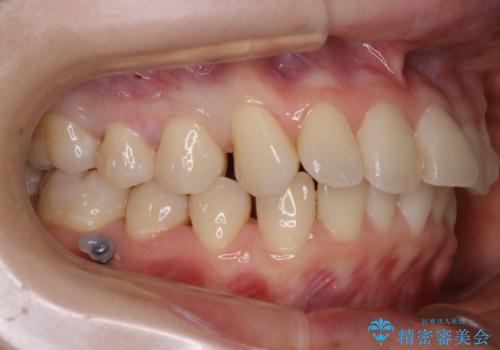

- 笑った時の歯の見え方を治したいとのことで矯正相談にいらっしゃいました。

一見そこまで大きなガタつきはないようにも見えますが、前歯の角度の不揃いや噛み合わせのズレなどから見え方に影響が出てしまっていました。

抜歯は全く必要のないレベルのガタつきだったため、マイクロインプラントを用いて歯全体を後方に移動させていくことできれいな歯並びを獲得することができました。